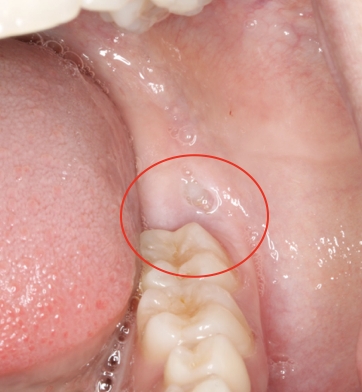

- Bleeding

- Infection

- Dry Socket